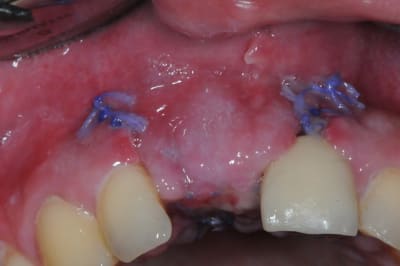

j'ai retrouvé, mais c'est le correspondant qui à posé l'implant et les photos sont pas top :(

j'essaie d'envoyer si ça marche

ceux sont les photos du correspondant .